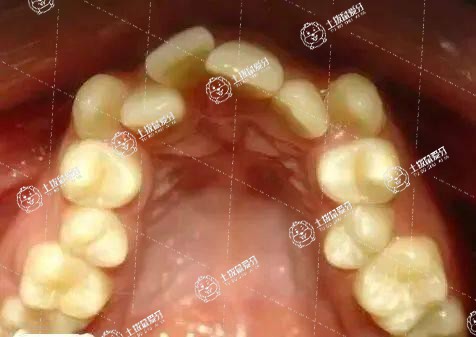

正畸解決的兩大主要問題是牙列不齊,也就是常說的牙列擁擠,以及嘴突、牙突,即齙牙。牙列擁擠是正畸的主要適應(yīng)癥之一,故牙齒擁擠適合正畸。能否正畸取決于患者的牙周情況及嚴(yán)重程度,若牙周不佳,則無法進行復(fù)雜的正畸治療,需要在牙周治療的基礎(chǔ)上,再次評估是否可以做正畸。但多數(shù)患者均無嚴(yán)重的牙周問題,所以牙齒擁擠對大部分患者而言可矯正。

牙齒擁擠是因牙床無足夠空間容納牙齒,故需去掉幾顆牙齒后將其排列整齊。部分患者介意拔牙,詢問不拔牙牙齒能否排整齊,是可以的,但牙齒被擠出向外齙,則由牙齒不齊變?yōu)辇_牙。所以臨床上針對牙齒不齊,尤其是擁擠較嚴(yán)重的患者,通常選擇拔牙矯正。